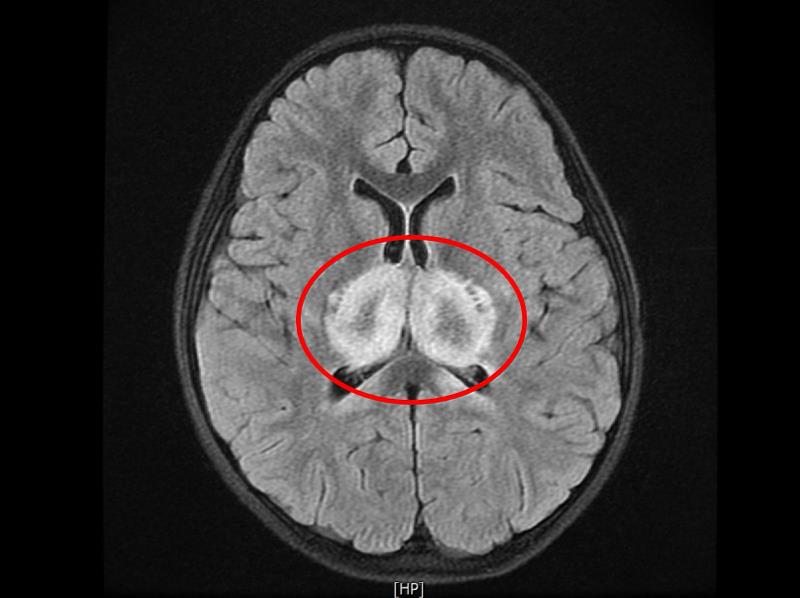

「解決危急病況只是第一步,後續還有一道道難關要解決,這是個漫長的過程。」花蓮慈院兒科病房主任陳明群表示,蔡小妹剛送至醫院急診時呈現無法說話、嗜睡、癲癇發作、抽筋、血壓下降、心跳偏低卻會時而飆升的狀態,生命徵象非常不穩定,核磁共振掃描影像顯示「視丘」區域發白,即此區塊正嚴重發炎。陳明群醫師指出,視丘是大腦的中繼站和樞紐,無論是感覺神經要將訊息傳回大腦,或運動神經要把指令從大腦傳出,都必須經過視丘轉換神經元傳遞訊號;因此若視丘有嚴重細胞損傷,將會大大影響患者生命健康。